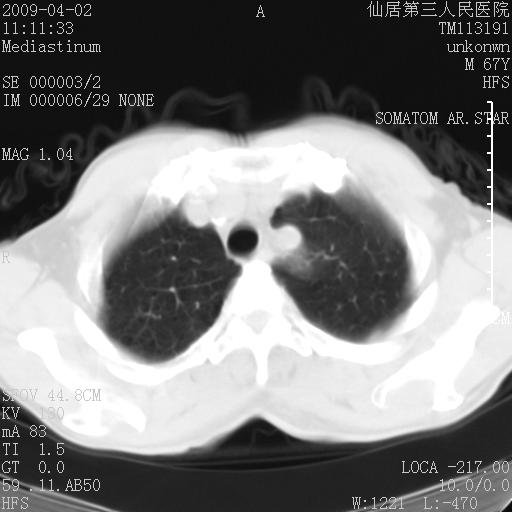

患者老年男性,乏力畏寒来诊,摄胸片示右下肺感染性病变,抗炎两周后复查胸片,无好转有进展。

后做ct平扫表现如下:

是否还要考虑肺间质纤维化,建议hrct扫描。

考虑间质性肺炎。

右肺下叶背段干酪性肺炎。请痰检[emb28]

考虑双肺间质性改变(间质纤维化?)伴右肺下叶感染。